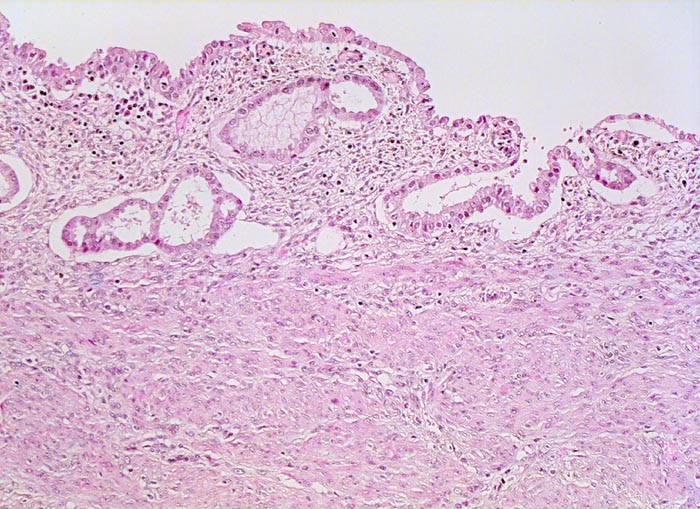

• Endomyometranes Gewebsfragment.

• Die rechte Seite des Uteruskavums wird ausgekleidet von flachem atrophem Endometrium. Im Cavum liegt ein Blutkoagel mit nekrotischem Detritus nach vorausgegangener diagnostischer Utersukurettage.

• Anstelle des Endometriums findet sich in der linken Hälfte des Uteruskavums ein Adenokarzinom bestehend aus architektonisch komplexen Drüsen. Die Drüsen liegen teils dos à dos ohne erkennbares Stroma zwischen zwei Drüsenschläuchen.

• Tumorzellverbände infiltrieren die glatte Muskulatur des Myometriums.

• Tumordrüsen ausgekleidet von mehrreihig angeordneten Tumorzellen mit hyperchromatischen polymorphen längsovalen Tumorzellkernen mit zahlreichen Mitosen. Die Morphologie der Tumordrüsen erinnert an proliferatives Endometrium.

• Anmerkung: Typischerweise ist das endometrioide Karzinom des Uterus als Folge des ursächlichen Hyperöstrogenismus assoziiert mit einem hyperplastischen Endometrium (siehe Präparat 148). Im Kurspräparat erscheint hingegen das nicht-neoplastische Endometrium nach vorausgegangener Kurettage atroph. Atrophes Endometrium findet sich sonst charakteristischerweise neben serösen Endometriumkarzinomen postmenopausaler Patientinnen. Das sollte der Kliniker dem Pathologen mitteilen: